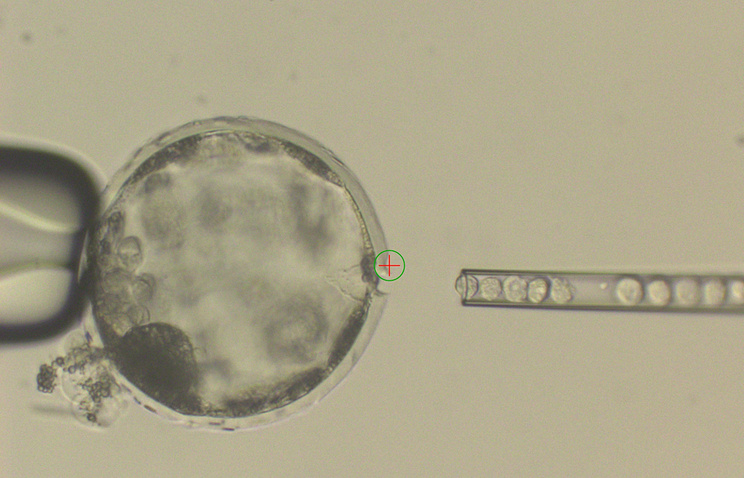

В ходе исследования выращенные при помощи iPS-клеток ткани сетчатки будут пересажены пациенту с возрастной макулярной дегенерацией. Для этого заболевания характерно повреждение центральной части сетчатки, что часто приводит к потере зрения.

Ткани для операции возьмут у человека, который является универсальным донором — его клетки могут прижиться в любом организме. Индуцированные стволовые клетки получают с помощью перепрограммирования клеток человека в эмбриональное состояние. После этого из таких клеток можно вырастить практически любую ткань.